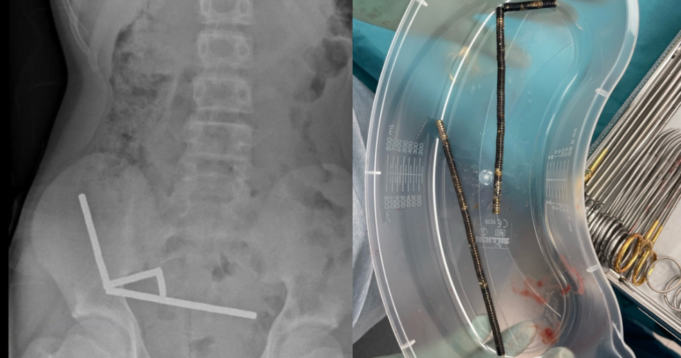

據《新西蘭醫學雜誌》最近發表的病例報告,一名13歲男孩因誤食數十塊高功率磁鐵而入院治療。醫生寫道,結果男孩失去了部分腸道。案件報告中沒有透露這名男孩的身份,他吃了 80 到 100 塊磁鐵。報告顯示,每個“高功率”磁鐵的尺寸為 5 x 2 毫米。吃了磁鐵後,這名少年連續四天出現腹部疼痛。到達醫院後,他告訴醫生他大約一周前吃了磁鐵。報告沒有指出他接受治療的醫院。病例報告沒有說明男孩是否解釋了他吃磁鐵的原因或方式。 X光片顯示男孩腹部有磁線。新西蘭醫學雜誌 吃大量磁鐵可能非常危險,因為它們可能會卡在體內並導致器官損傷或其他並發症。報告顯示,食用大量磁鐵的患者往往需要手術干預。特別危險的是高功率磁鐵,它們通常作為成人的桌面玩具出售。 2019 年,哥倫比亞廣播公司新聞報導稱,它們的強度比傳統冰箱貼強五到十倍。掃描顯示,磁鐵在少年的腸道和大腸的起始處以四根鏈的形式連接在一起。報告稱,他體內的磁鐵數量干擾了一些成像,因此醫生進行了探查手術。在手術過程中,外科醫生髮現磁鏈導致腸道和結腸壓力性壞死。當組織因長時間承受過大壓力而死亡時,就會發生壓力性壞死。外科醫生成功移除了磁鐵,男孩從手術中康復了。報告顯示,他住院八天后就出院了。正如報告中指出的那樣,這些高功率磁鐵的銷售在新西蘭已被永久禁止,但該禁令很難執行,因為這些磁鐵可以在網上輕鬆而廉價地購買。男孩告訴醫生他是在 Temu 網站上購買的磁鐵。特穆告訴哥倫比亞廣播公司新聞,他們“很遺憾得知所報導的事件,並祝愿男孩早日完全康復。” Temu 發言人周六對哥倫比亞廣播公司新聞表示,無法獨立核實這些磁鐵是否是在該網站上購買的。經過內部審查後,該公司確定目前可運送到新西蘭的報價符合該國的法規。該公司表示:“雖然這些產品可以合法銷售,但如果吞嚥它們可能會很危險,這就是為什麼我們支持提高公眾對磁鐵安全意識的努力。”磁鐵被從男孩的胃中取出。新西蘭醫學雜誌發言人周五表示:“我們非常重視產品安全,並持續監控我們的平台,以確保賣家遵守其經營市場的安全法規。”亞馬遜和全球速賣通等在線零售商列出了可運送到新西蘭的高功率磁鐵。美國消費品安全委員會一直致力於限制高功率磁鐵在美國的銷售。 2014年,該機構發布了針對高功率磁鐵組的禁令,但兩年後被法院推翻。 2022年9月,該機構制定了磁鐵的強制性安全標準。該規則為任何帶有鬆動或可拆卸磁鐵的產品(包括用於娛樂和緩解壓力的產品)設定了功率限制。美國消費品安全委員會還認為磁鐵存在安全風險,並已多次召回含有磁鐵的產品。